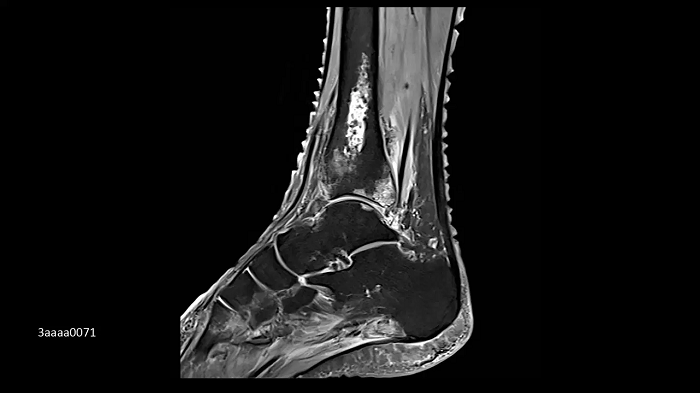

Foot/ankle imaging with the new Ultraflex Coils

The new coils allow ultra-high-density orthopedic imaging with the flexibility to apply in different anatomical regions.

Image Credit: Radiologie München Harlaching, Munich, Germany